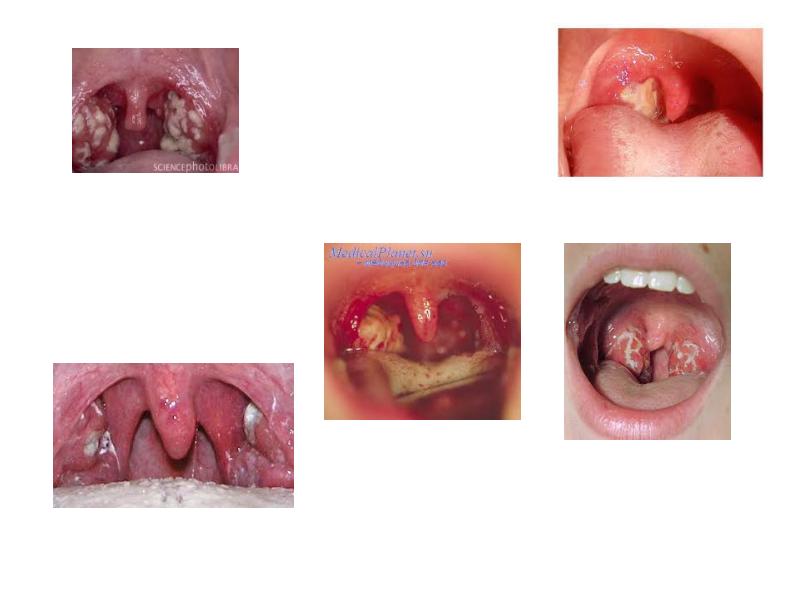

- 24. Язвенно-некротическая (гангренозная) ангина Причиной язвенно-некротической ангины Симановского-Плаута-Венсана считают симбиоз веретенообразной палочки

- 25. Язвенно-некротическая ангина

- 26. Некротическая ангина.